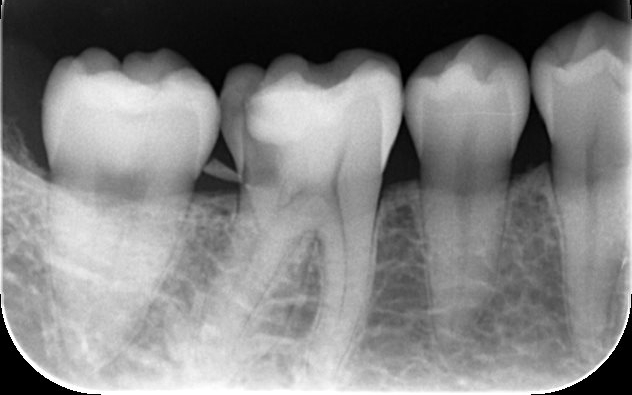

被せ物(クラウン)の素材には、天然歯に近い透明感をもちながら、優れた耐久性を兼ね備えたジルコニアセラミックを採用しました。

最後に、完成したジルコニアセラミッククラウンを装着し、噛み合わせや見た目などに問題がないことを確認して、治療を終了しています。